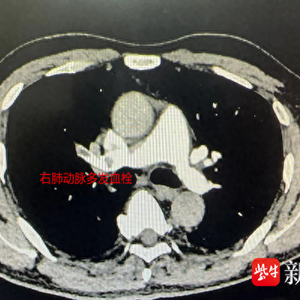

50岁的周先生的右腿水肿已一个月有余,加上开始有胸闷症状,于是来到江苏省中西医结合医院就诊。心血管科副主任医师吴溧兴在接诊中了解到,周先生是一名长途车司机,一般四个小时才停车休息一下,开车时也很少饮水,还有长期的饮酒和吸烟史。通过双下肢动静脉彩超和肺动脉CTA检查发现,他的右侧下肢股总静脉及其以下分支血栓形成,右肺动脉主干、右肺动脉及左下肺多分支肺动脉栓塞。随后,周先生被安排住院治疗,经过积极的抗凝治疗,他下肢水肿及血氧等各项指标逐渐恢复正常。出院时,吴主任还特别叮嘱周先生继续口服抗凝药物,暂时不要长途驾驶,要戒烟戒酒,足量饮水,适当活动。一月后,周先生再次来到医院复查,下肢静脉彩超显示血栓消失。